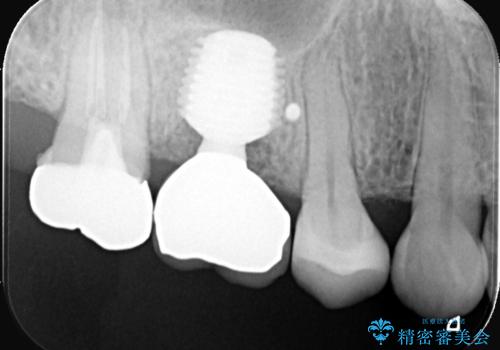

前歯の破折も1日で解決!抜歯即時インプラントで自然な笑顔へ